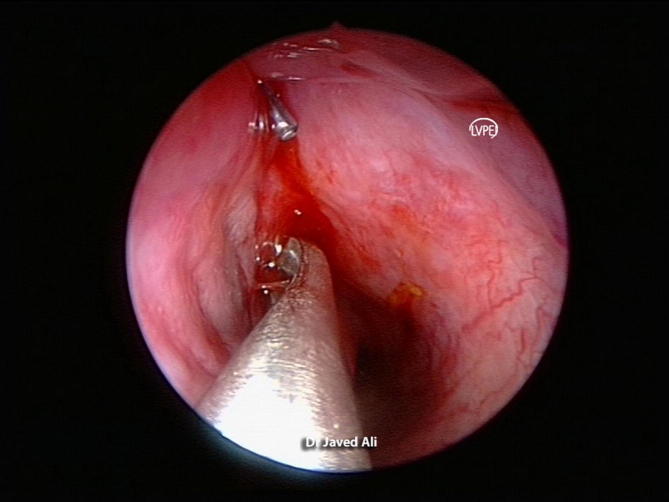

Figure 6.

Endoscopic view of the dilated nasolacrimal duct opening. Note the silicone tube exiting the duct opening in inferior meatus.